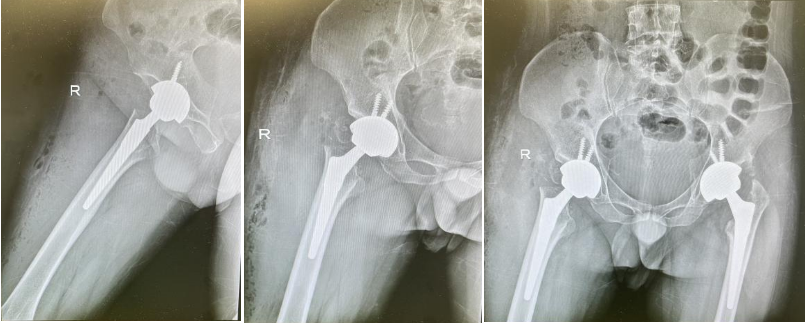

图片

手术成效在术后即刻显现:术中直接测量确认双下肢长度完全对称,困扰患者的5厘米差距被精准消除;术后第3天,患者便成功扔掉增高垫,在助行器辅助下实现双足平稳着地行走。得益于微创手术的创伤优势与团队的快速康复方案,患者术后疼痛轻、肌力恢复迅速,步态训练进展显著,很快实现协调行走。

此次双髋序贯精准重建的圆满成功,不仅是郝阳泉教授团队技术实力的集中体现——从复杂病例的系统评估、分期诊疗,到前沿技术的创新应用、毫米级精准操作,每一个环节都彰显了团队在复杂关节重建领域的领先水平;更印证了团队将个体化精准医疗与快速康复理念深度融合的诊疗特色。未来,骨坏死与关节重建病区将持续以先进技术为支撑,为更多双侧髋关节重症患者提供“行走的平等与尊严”,筑牢国内骨坏死与关节重建领域的技术高地。